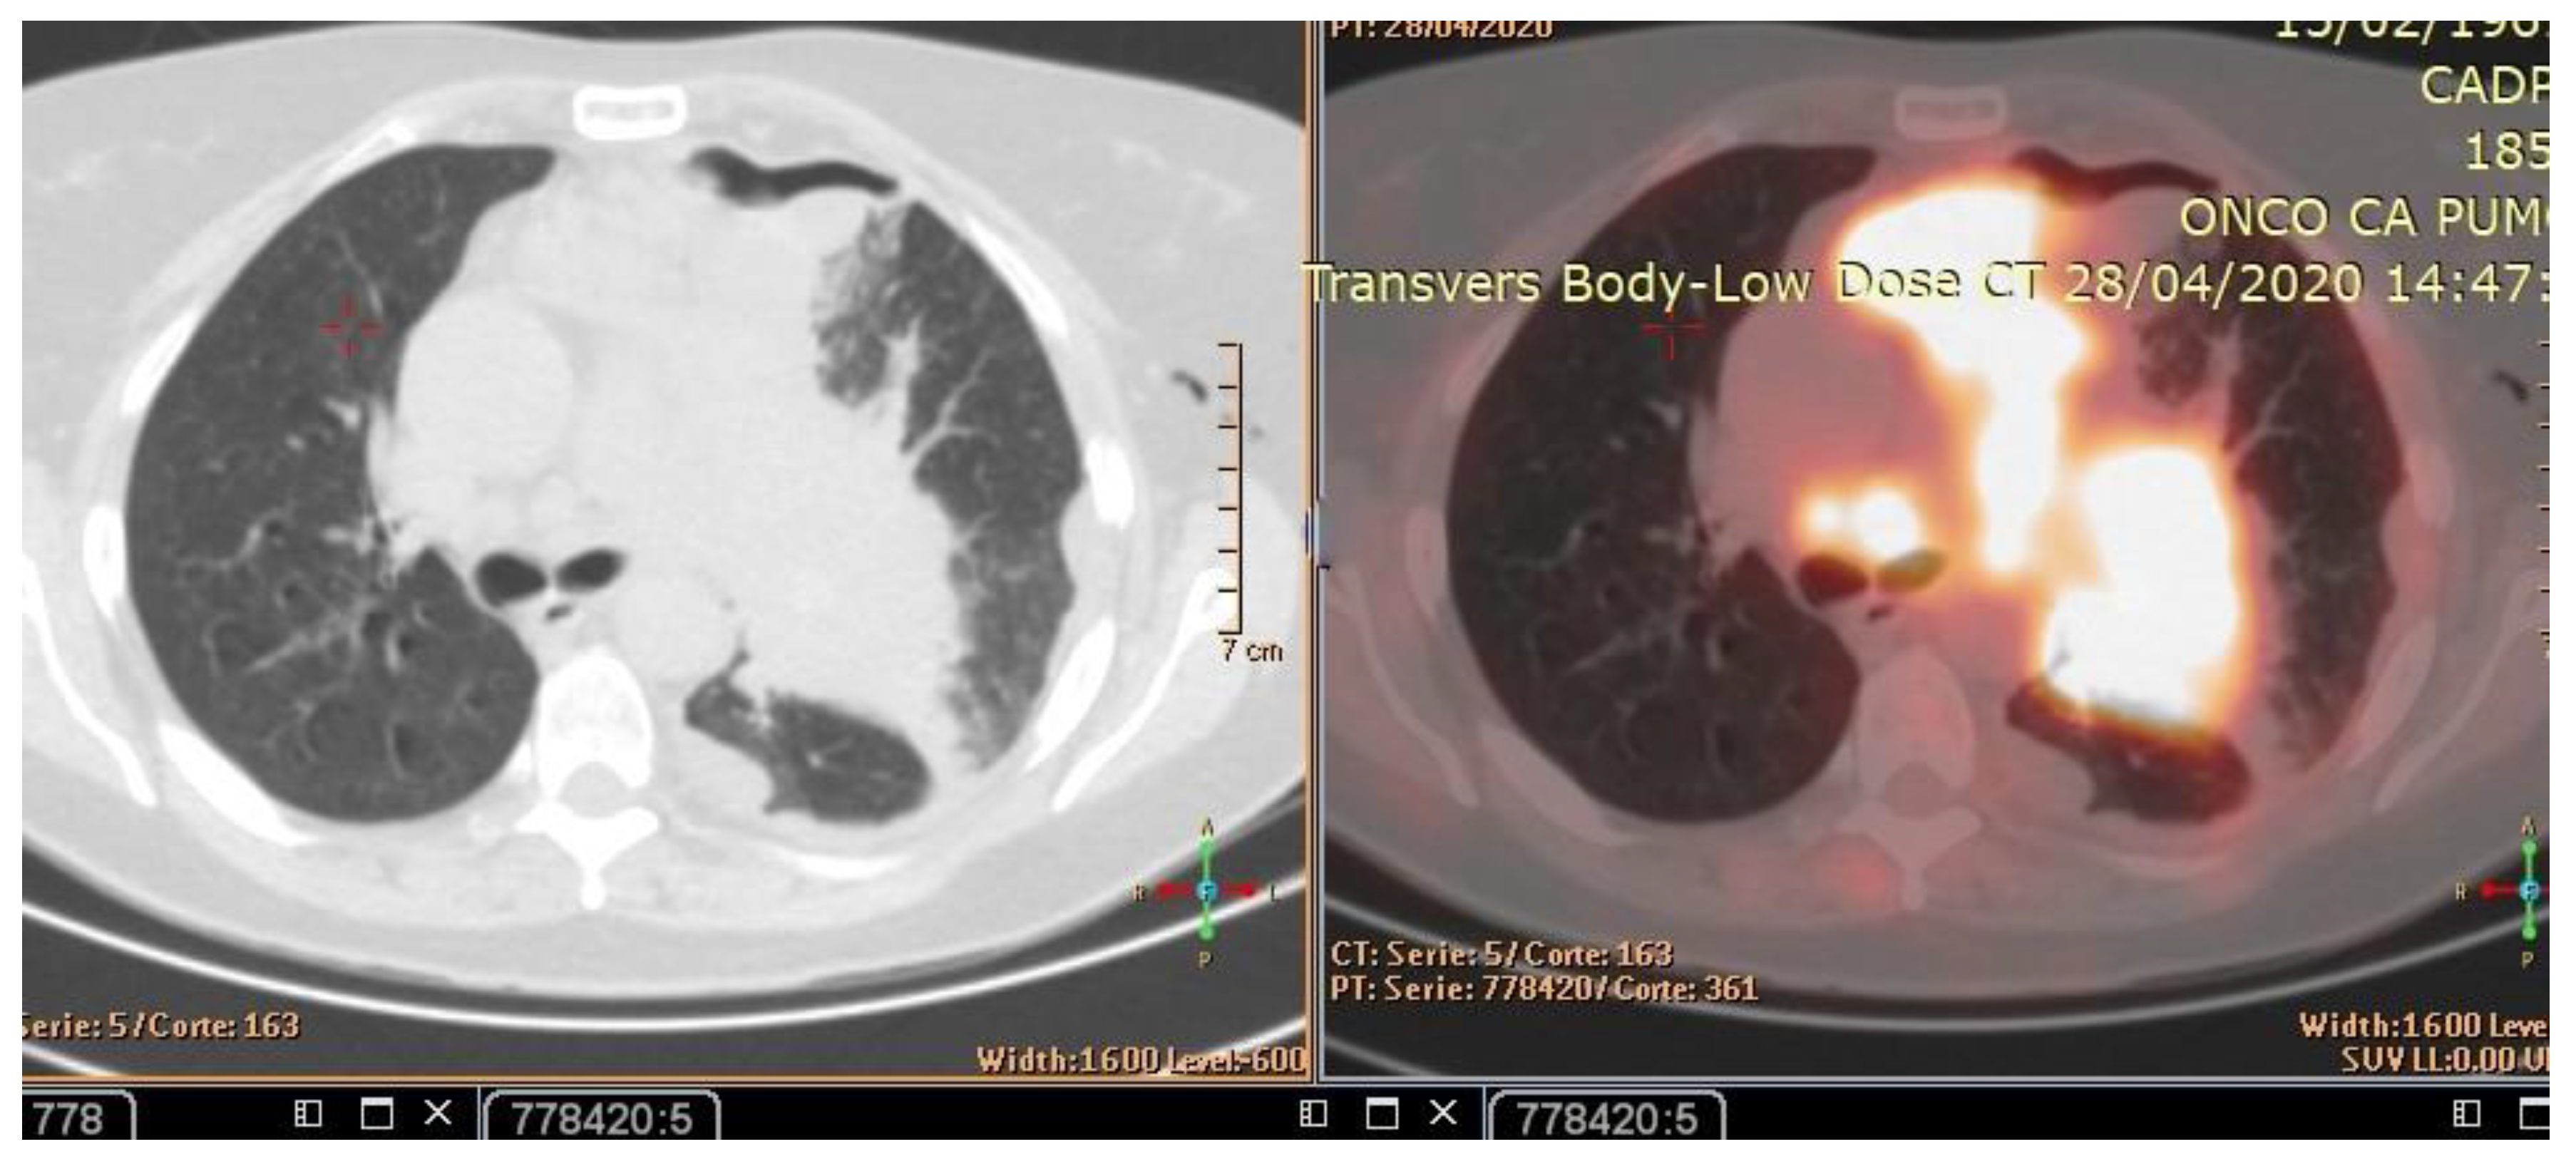

The patient’s history and physical examination as well as recent imaging evaluation should be well evaluated. Chest CT is the key imaging modality for evaluating lung tumor size and the location of lesions. Because of the complaint also of dysphagia, we conducted a CT scan of the chest, abdomen, and pelvis with means of contrast. A biopsy was taken as advised by [52]. The presence of small cell lung cancer, stage IVA (T4 N3 M1a) was confirmed. PET-CT and CT scans show images of a hypermetabolic left pulmonary hilar tumor (Figure 2).

Figure 2. CT scan (left) and Pet-CT (right) images of hypermetabolic left pulmonary hilar tumor from a female SCC patient.